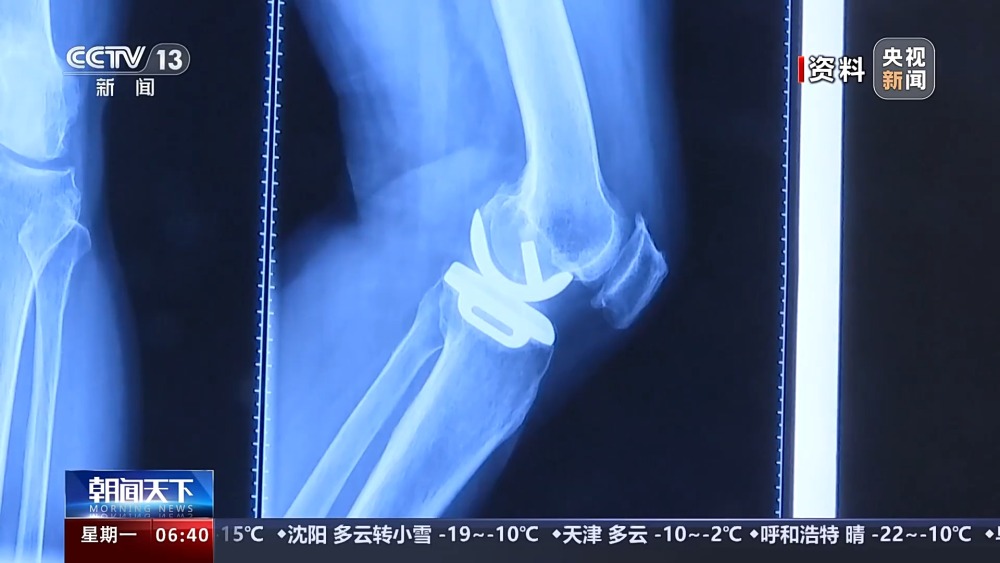

目前,我國(guó)有超過(guò)1億人患有骨關(guān)節(jié)炎,65歲以上人群中,骨關(guān)節(jié)炎發(fā)病率接近50%。以前,嚴(yán)重骨關(guān)節(jié)炎患者主要通過(guò)膝關(guān)節(jié)置換手術(shù)來(lái)維持行走等基本功能。膝關(guān)節(jié)置換手術(shù)存在術(shù)后關(guān)節(jié)僵硬、長(zhǎng)期疼痛等問(wèn)題。保膝治療包括藥物、理療等保守治療,以及手術(shù)治療。

保膝手術(shù)主要包括截骨術(shù)和單髁置換術(shù),其中截骨術(shù)在解決患者疼痛癥狀的同時(shí),阻止下肢異常應(yīng)力對(duì)膝關(guān)節(jié)的進(jìn)一步損傷,膝關(guān)節(jié)內(nèi)所有軟骨韌帶、半月板都得到了保留。內(nèi)側(cè)單髁置換術(shù),使膝關(guān)節(jié)外側(cè)健康的軟骨和半月板得到了保留,膝關(guān)節(jié)內(nèi)外側(cè)的韌帶維持原有狀態(tài),患者康復(fù)后,擁有正常的膝關(guān)節(jié)功能。